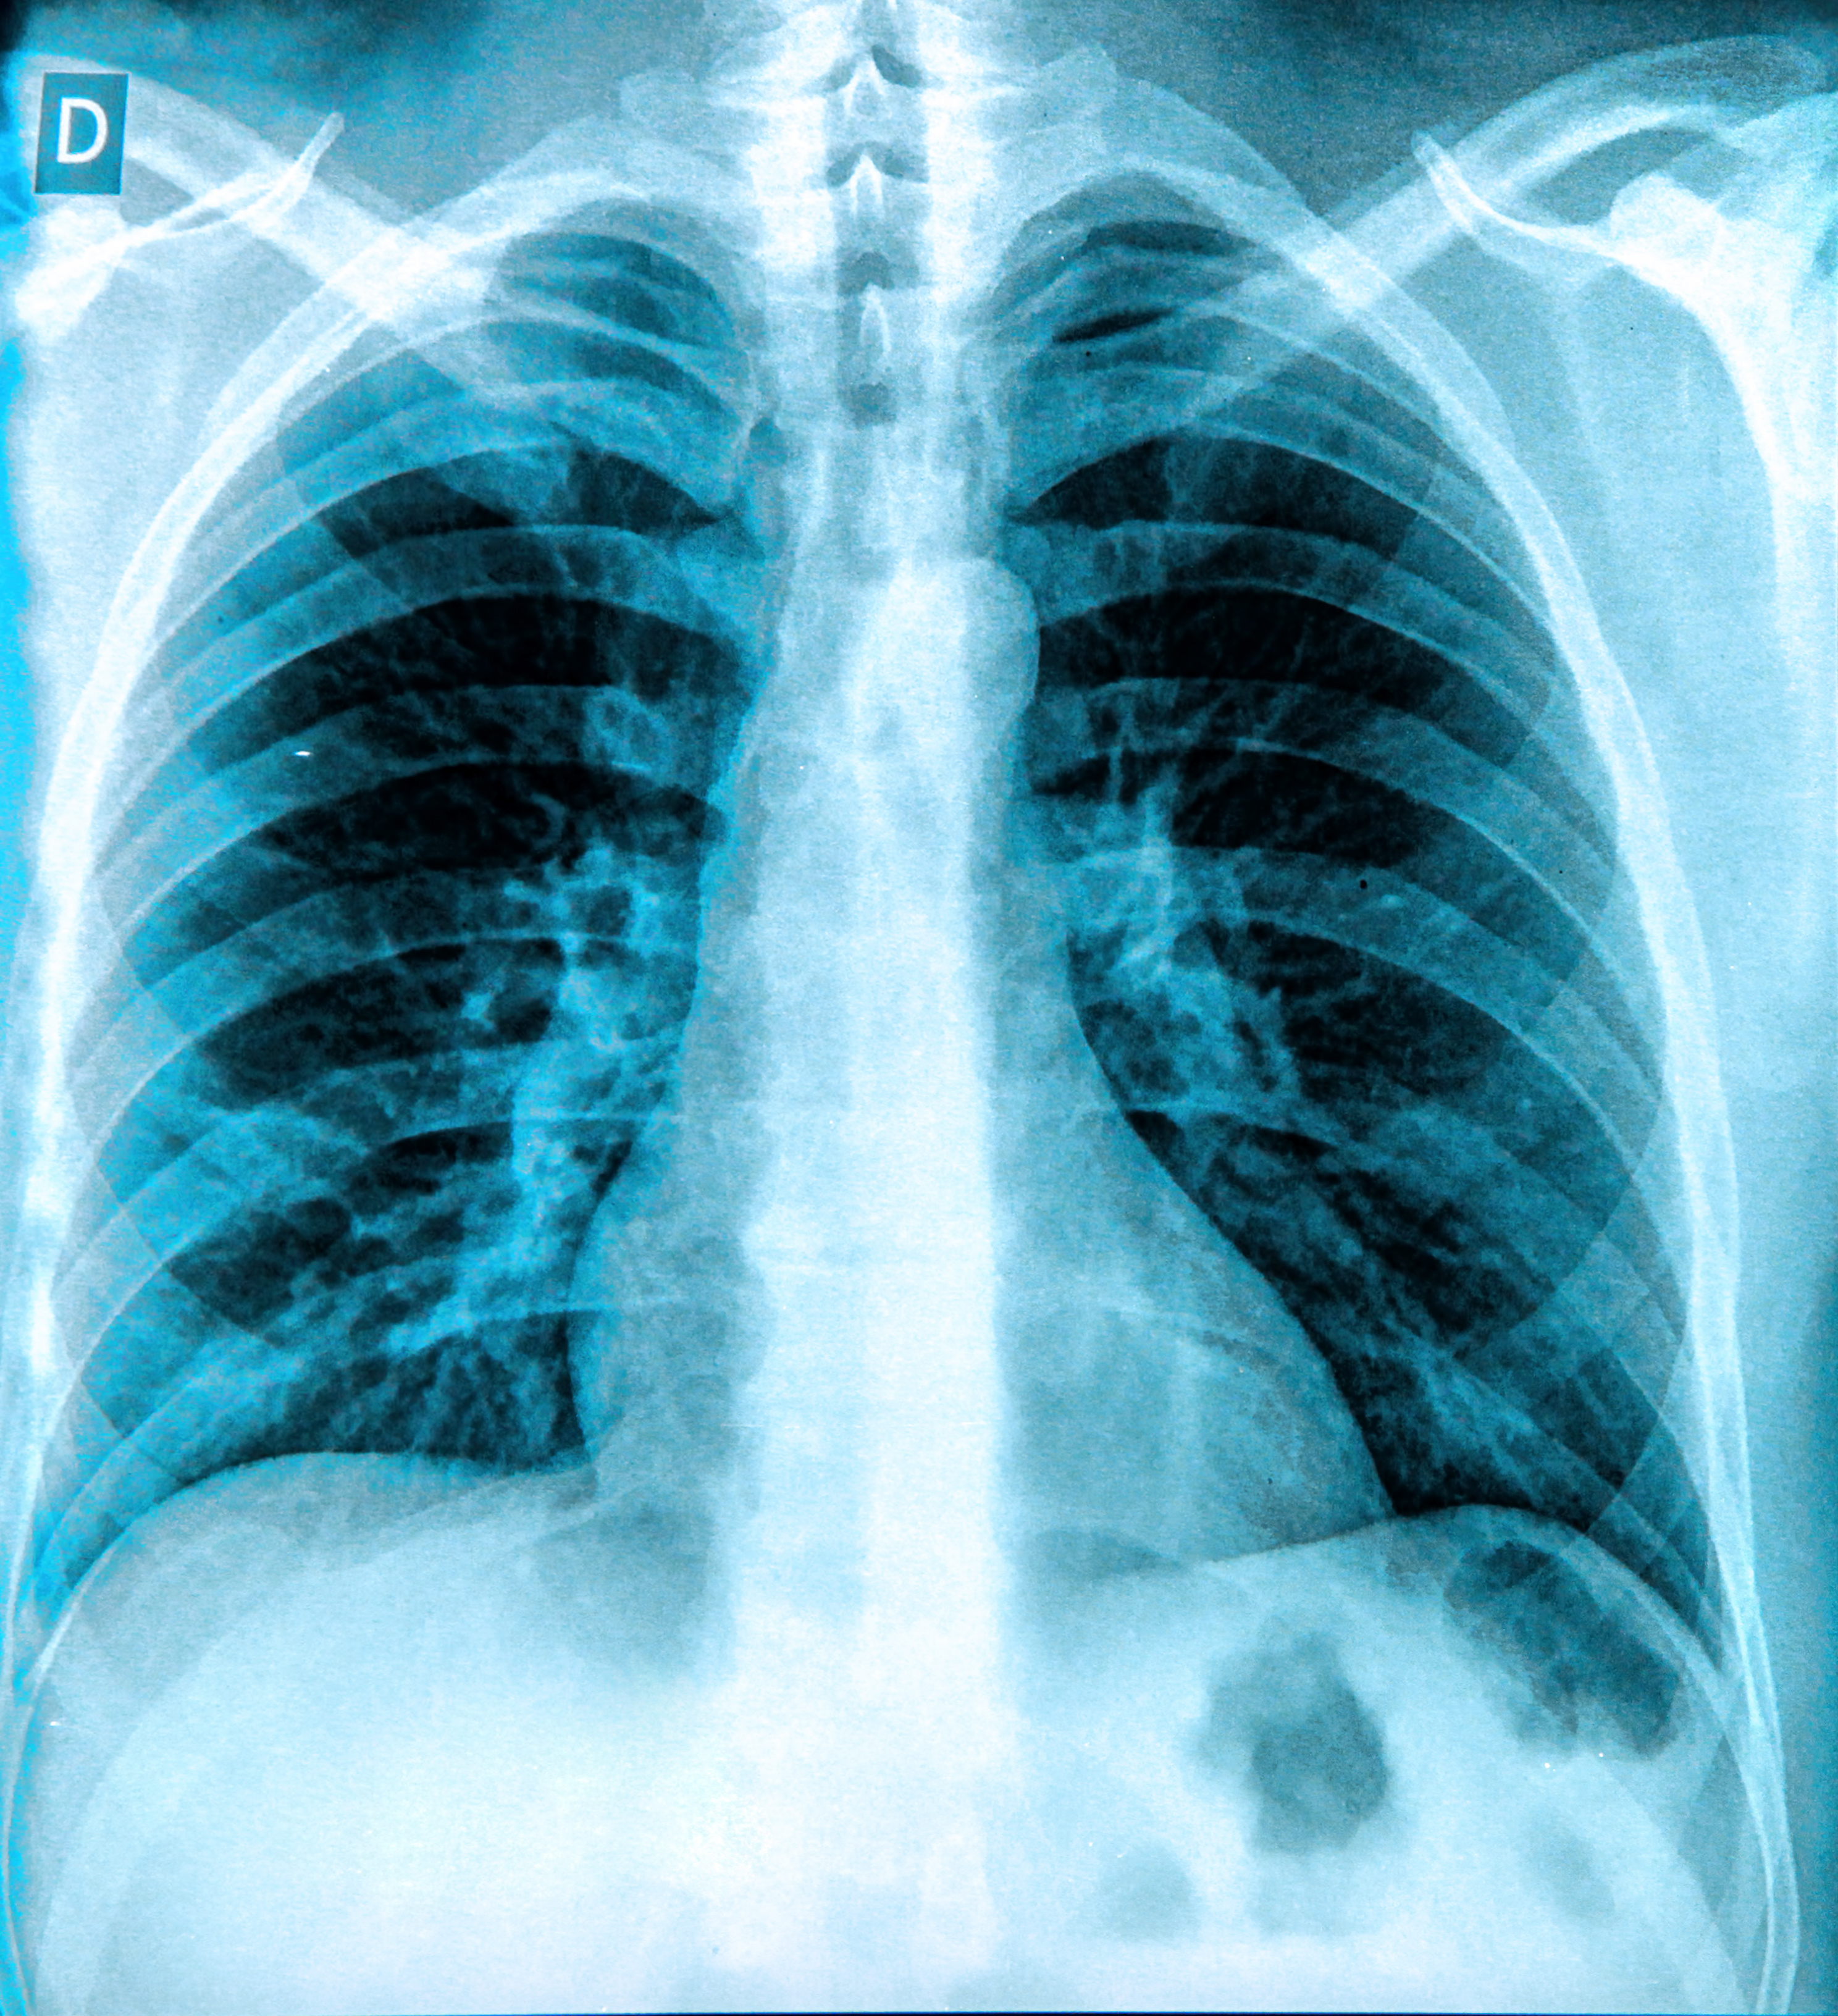

The product, which is part of Qure.ai’s AI-based lung cancer suite for chest x-ray and CT, is designed to detect, measure, and track lung nodules, which may be indicative of lung cancer.